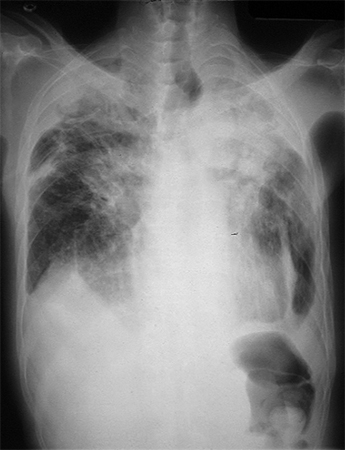

RT de fibrosis masiva progresiva debido a exposición a la sílice o al carbón

De la colección personal de Kenneth D. Rosenman, Michigan State University